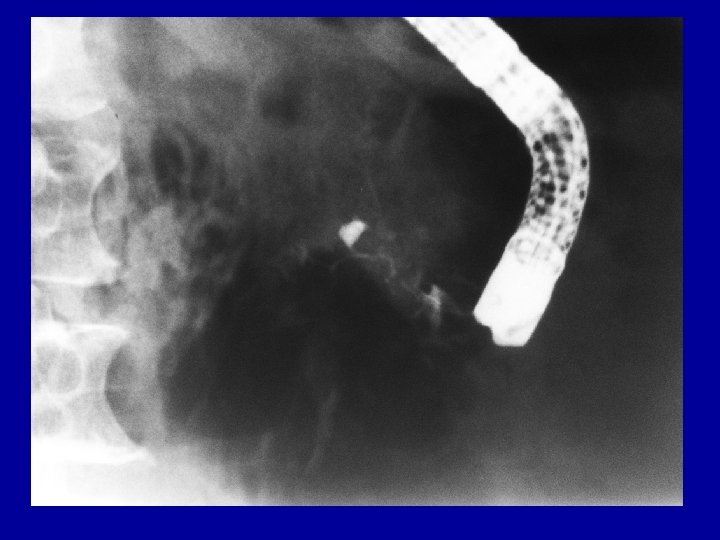

Case report II. • 1992 Dec. Lundh test: no exocrine insufficiency, glucose loading: 4. 4 -7. 7 -7. 5 -8. 1 -10. 1 mmol/l • US + CT: obstructive pancreatitis with 5 mm diameter dorsal pancreatic duct, enlarged parenchyma, no calcification. • ERCP: duodenal compression with enlarged pancreatic head, swollen parapapillary duodenal mucosa, unsuccessful cannulation of the papilla, normal biliary outflow through the large choledocho-duodenostomy

Case report IV. • 2004 Aug. acute relapsing pancreatitis • CT: parapapillary inflammation + calcification, moderate proximal pancreatic duct dilatation • Non-insulin dependent diabetes mellitus. ALP: 447 U/l, GGT: 178 U/l • Unsuccessful ERCP in another institution

Case report V. • 2004. Okt. ERCP: suprapapillary stricture of common bile duct with normal outflow at the choledocho-duodenostomy, P. divisum • Patulous secondary papilla with suprapapillary stenosis of the dorsal duct • Secondary papillotomy with needle-knife, dilation + 8 F pancreatic stent with jejunal feeding tube. • 2004 Nov. dilation + 10 F pancreatic stent into the dorsal duct (double stenting 8 F + 10 F)